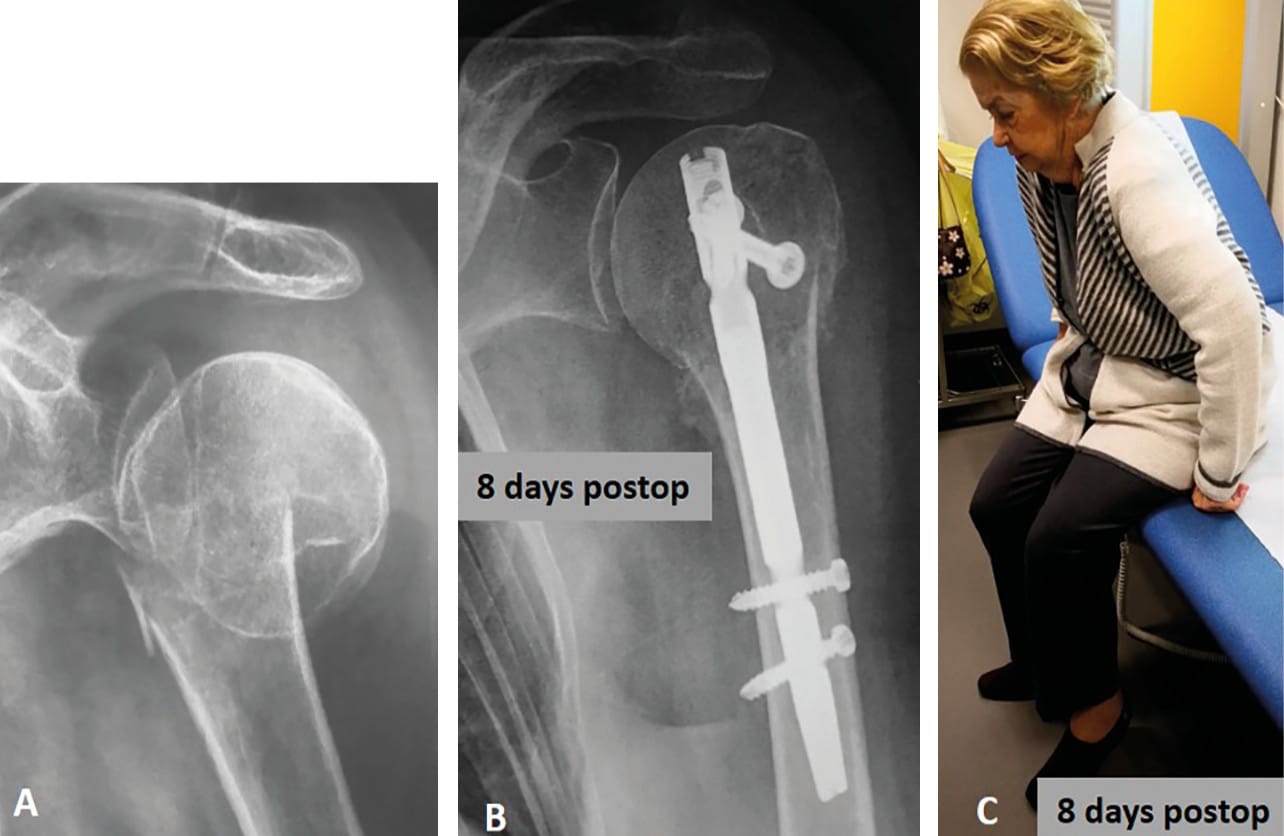

After assessment of the reduction and the nail’s depth under fluoroscopy, the guide wire is retrieved and the two distal screws were first placed in the diaphysis. Once distal fixation is obtained, gentle retrograde impaction of the distal to the proximal segment via a sliding slap-hammer is then performed (“backslap” hammering) to allow intraoperative immediate compression of the fracture site (Figure 5). Finally, proximal fixation is obtained by percutaneous insertion of a minimum of two proximal locking-screws via the attached jig. Postoperatively, the shoulder is placed in a sling for 1 week postoperatively. Passive elbow and shoulder mobilization with pendulum exercises (5 times a day and 5 minutes per session) is performed immediately. Patients are encouraged to remove the brace at day one, and to use their hand for ADLs.

At last review, mean active forward elevation was 145° (range: 90°-180°), and external rotation 50° (range: 20°-80°). Mean Constant-Murley Score and subjective shoulder value (SSV) were 71 (range: 43-95) and 80% (range: 50-100%), respectively. At the last follow up, the mean SSV was 80% ± 12 (Figure 8).

Our study shows that antegrade insertion of third-generation IMN through a percutaneous approach provides high rate of fracture healing, excellent clinical outcome scores with low rates of complications. Such IM nail has a low-profile and straight design, and the proximal screws are tuberosity-oriented and locked by polyethylene bushing inside the proximal part of the nail. We found several advantages for using this new generation of humeral IMN through a percutaneous approach for the treatment of displaced two-part surgical neck fractures, including minimal soft-tissue damage with minimal risk of humeral head osteonecrosis (only one case in our series), short operative time (42 minutes in average, including our learning curve) and improved cosmesis (Figure 9 and 10).